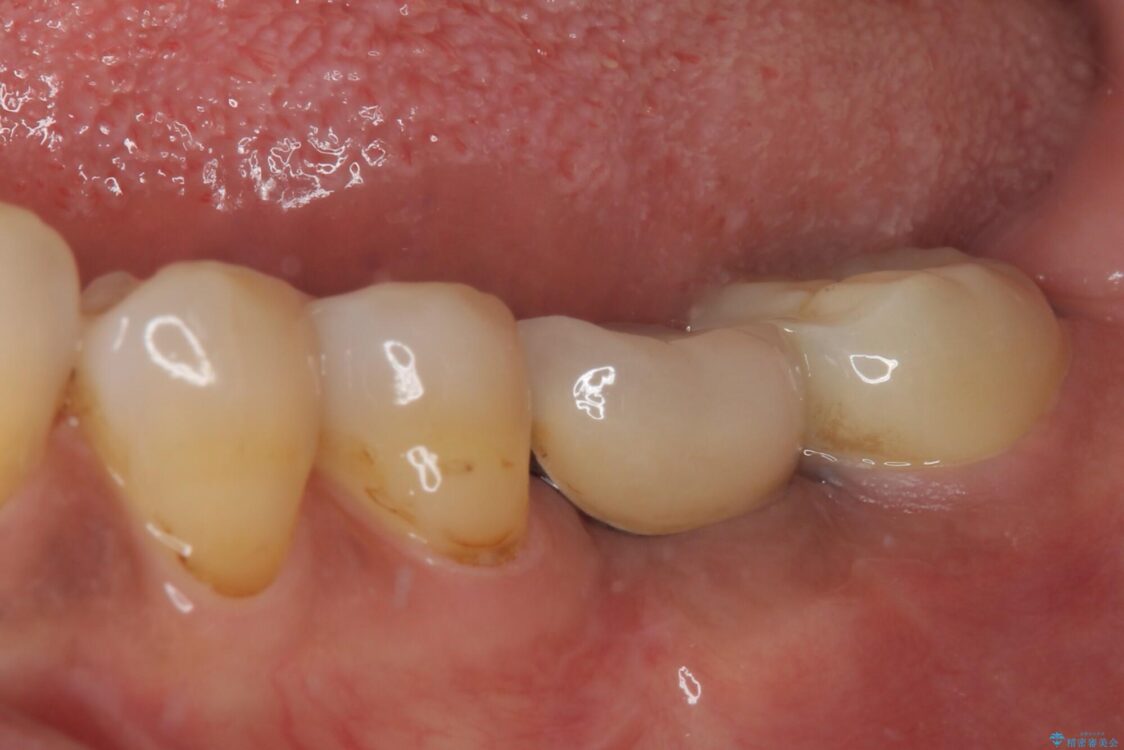

銀歯の装着されている奥歯がしみるとのことで来院された患者様です。

銀歯周辺の歯が欠けており、むし歯も進行している状態であったので、オールセラミッククラウンにて補綴治療を行うこととしました。

• しみる奥歯 オールセラミッククラウンによる補綴治療 治療前画像